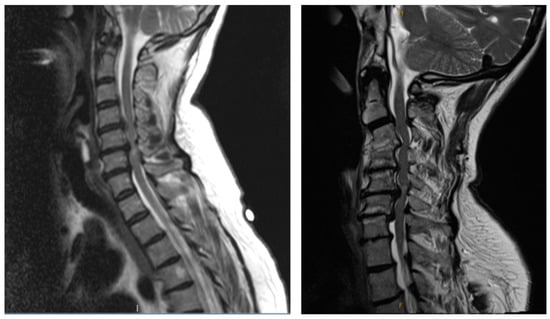

6.3. Advanced Imaging and Diagnostic Tests

- He, B.; Sheldrick, K.; Das, A.; Diwan, A. Clinical and Research MRI Techniques for Assessing Spinal Cord Integrity in Degenerative Cervical Myelopathy—A Scoping Review. Biomedicines 2022, 10, 2621. [Google Scholar] [CrossRef] [PubMed]

- Martin, A.R.; Tetreault, L.; Nouri, A.; Curt, A.; Freund, P.; Rahimi-Movaghar, V.; Wilson, J.R.; Fehlings, M.G.; Kwon, B.K.; Harrop, J.S.; et al. Imaging and Electrophysiology for Degenerative Cervical Myelopathy [AO Spine RECODE-DCM Research Priority Number 9]. Glob. Spine J. 2022, 12, 130S–146S. [Google Scholar] [CrossRef]